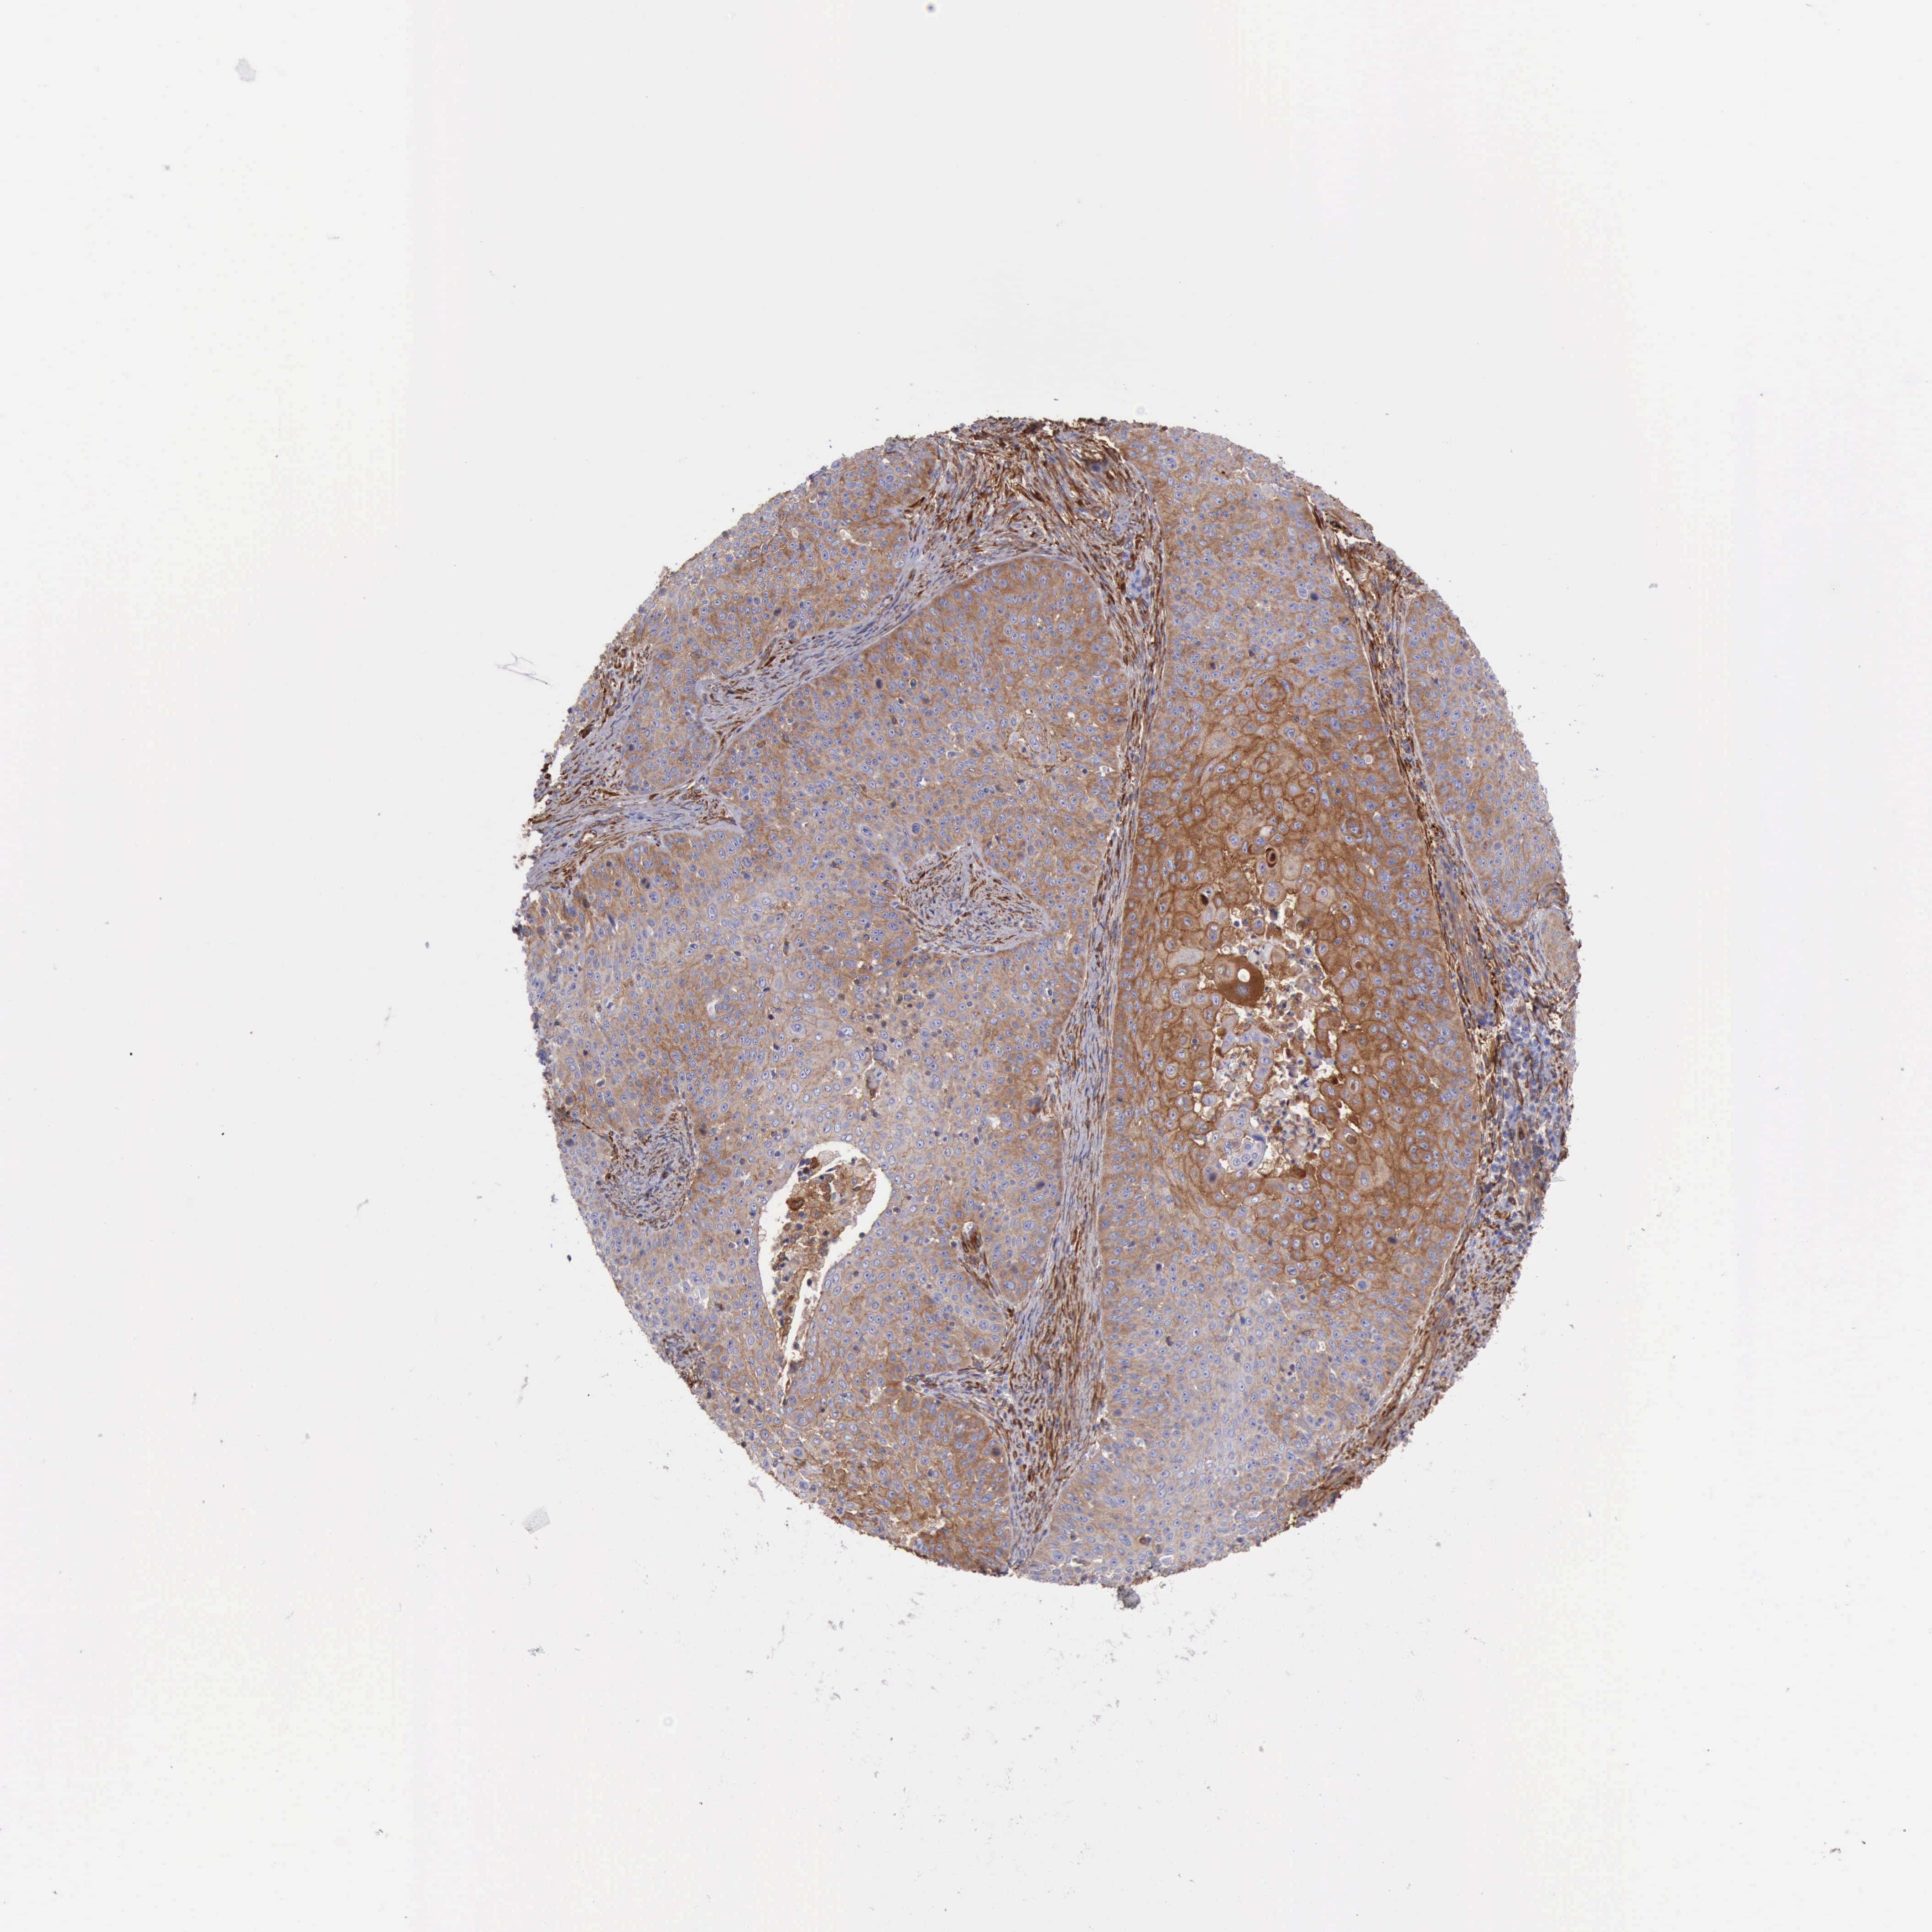

SKIN CANCER - Protein expressioni

A mouse-over function shows sample information and annotation data. Click on an image to view it in a full screen mode. Samples can be filtered based on level of antibody staining by selecting one or several of the following categories: high, medium, low and not detected. The assay and annotation is described here.

Each image is clickable and will lead to virtual microscopy that enables deeper exploration of all samples and also displays staining intensity scores, fraction scores and subcellular localization as well as patient and tissue information for each sample.

Antibody HPA001115

Staining

High

Medium

Low

Not detected

Intensity

Strong

Moderate

Weak

Negative

Quantity

>75%

75%-25%

<25%

None

Location

Nuclear

Cytoplasmic/membranous

Cytoplasmic/membranous,nuclear

Squamous cell carcinoma, NOS

Basal cell carcinoma